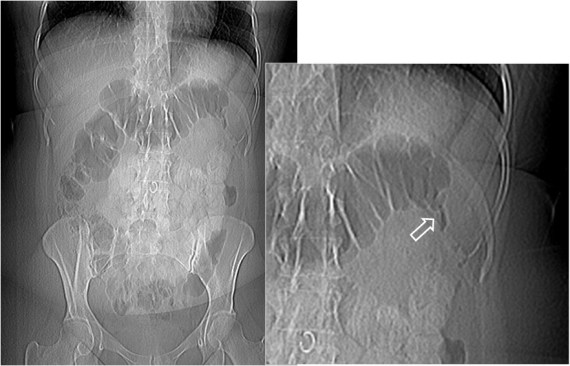

SIGNO DE LAS BURBUJAS DE JABÓN o POMPAS DE JABÓN o SIGNO DE NEUHAUSER

En el íleo meconial, en la radiografía simple de abdomen, la mezcla de meconio con el gas intestinal da un aspecto moteado como pompas o burbujas de jabón.

En la literatura también aparece en singular, Signo de la burbuja de jabón, y como Signo de Neuhauser. Aunque clásicamente se refiere al íleo meconial, no es un signo específico, pudiendo aparecer también en la enfermedad de Hirschsprung, en la atresia ileal y en la enteritis necrotizante.